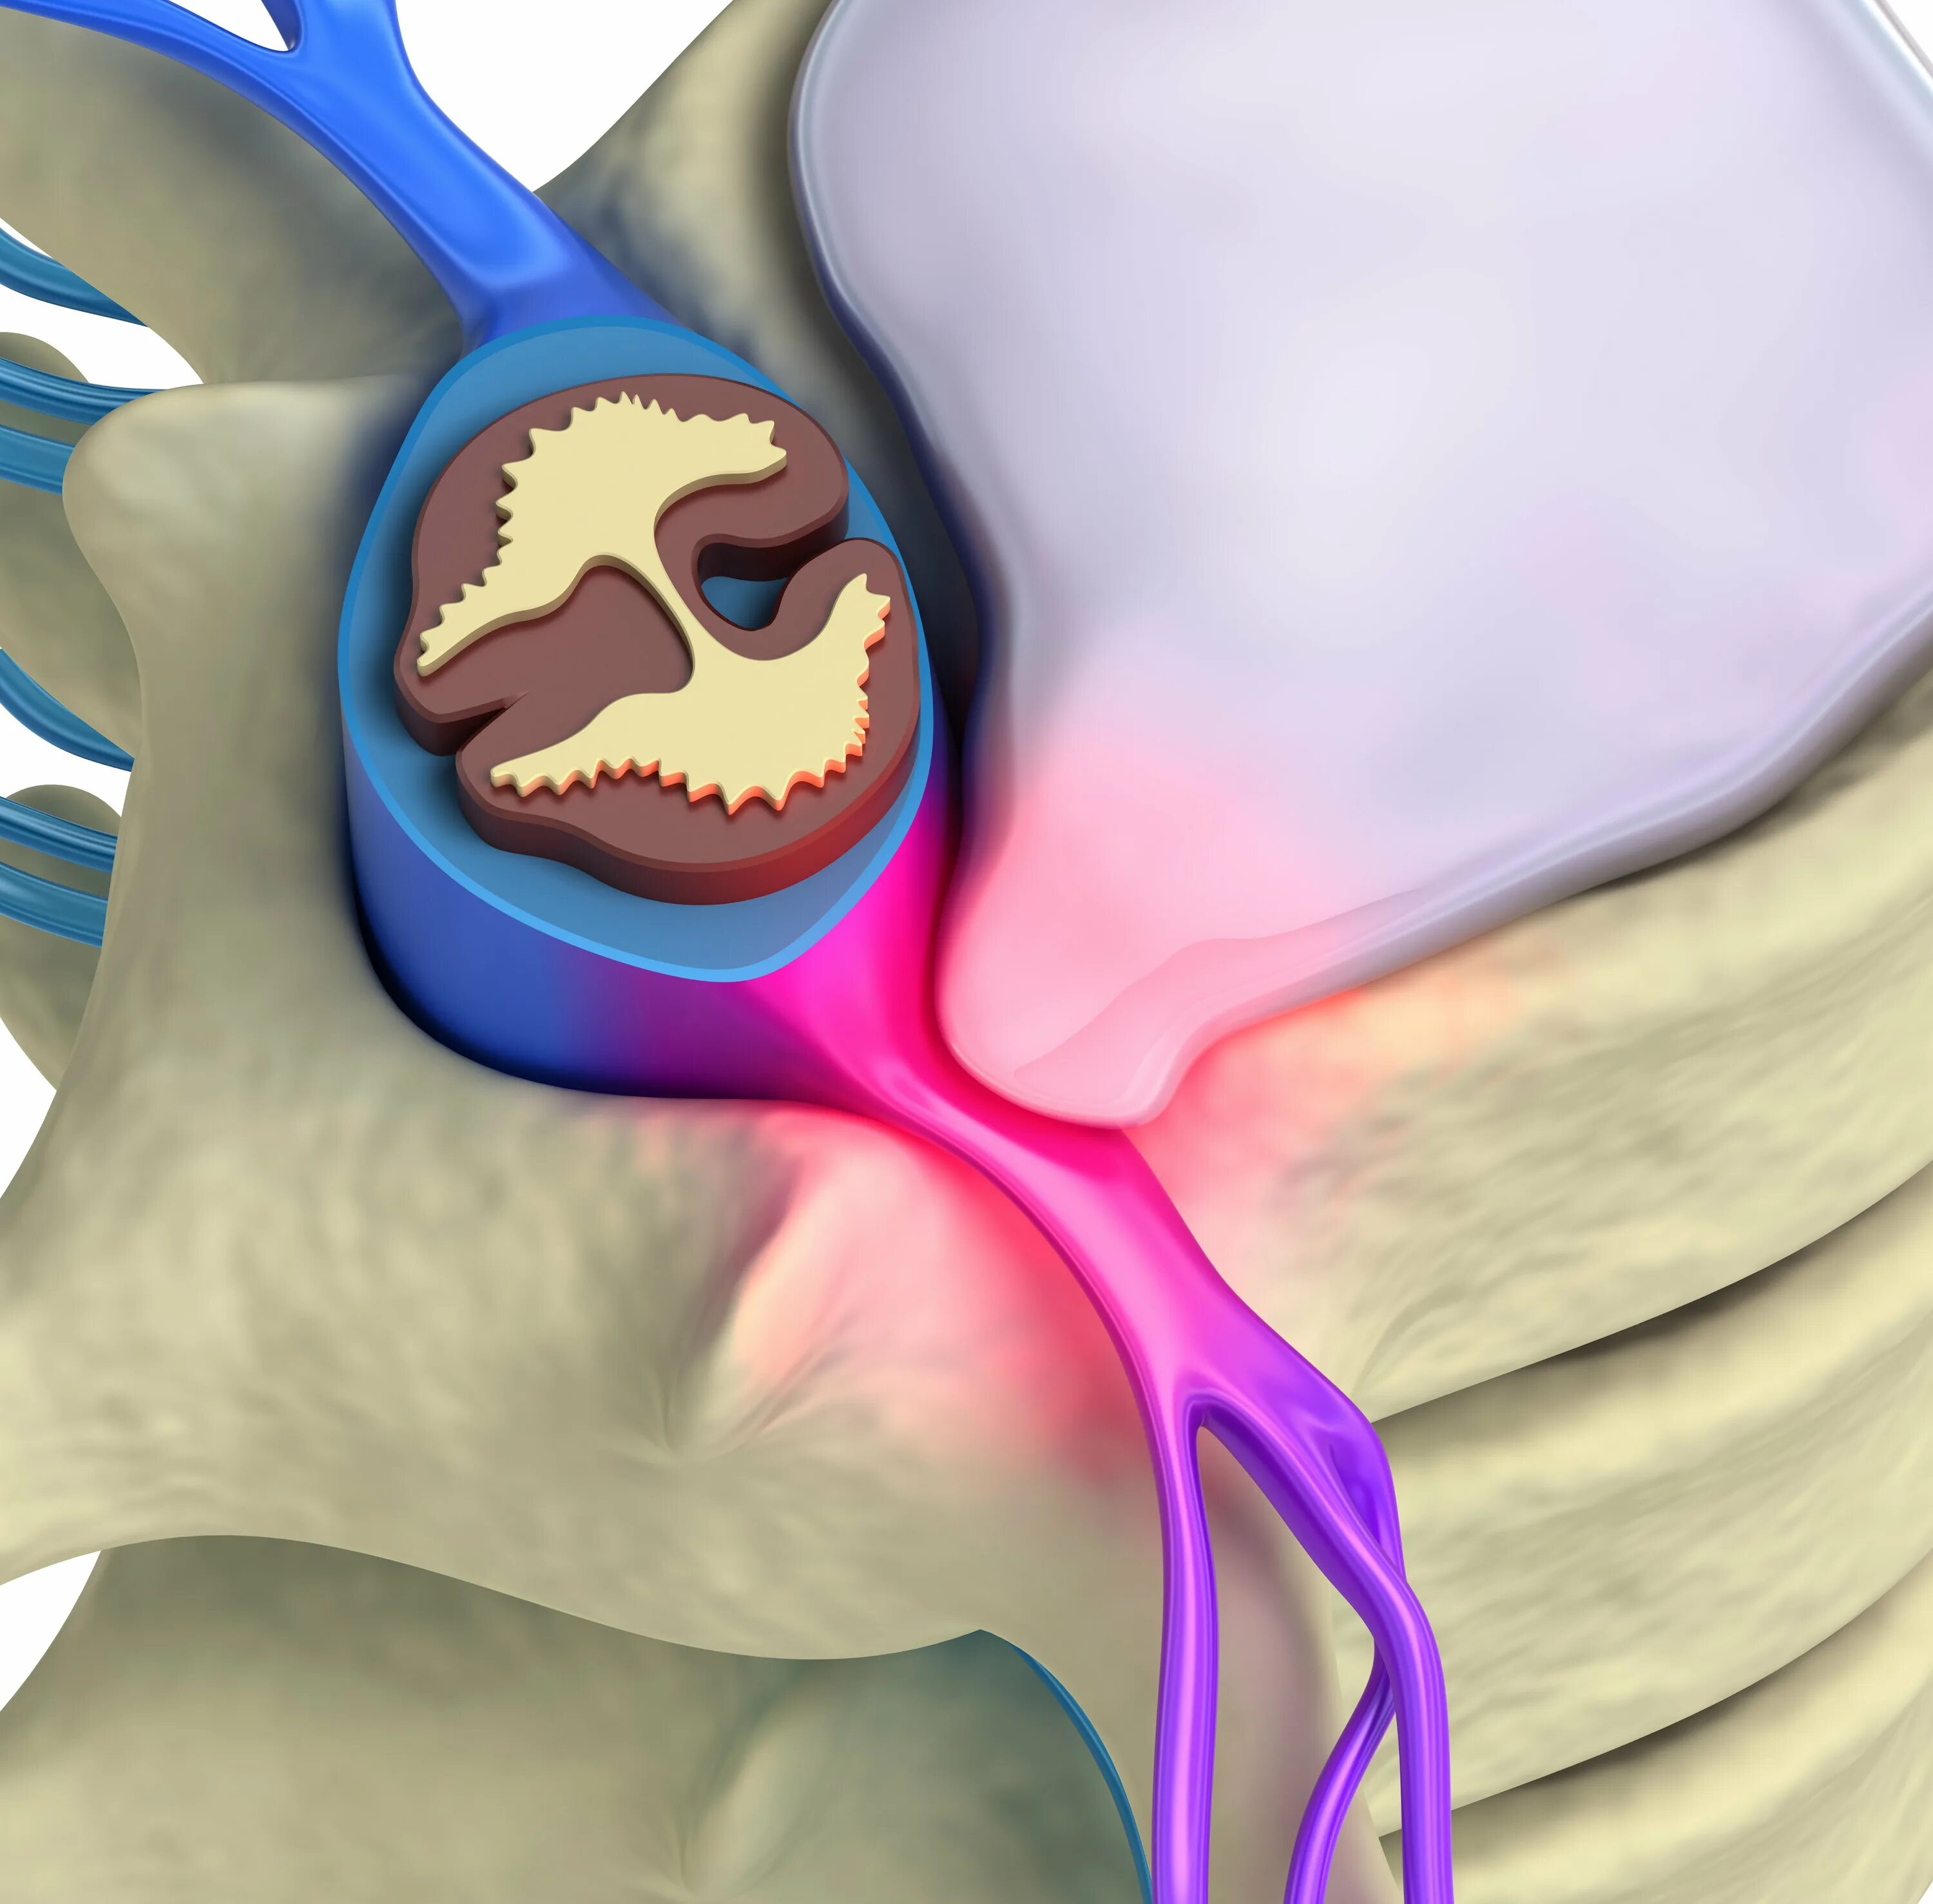

Диффузная протрузия межпозвонковых